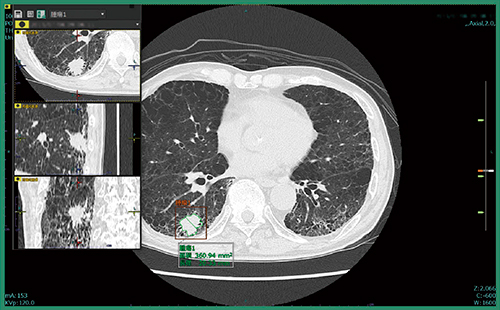

肺結節CADeのプロトタイプは,対象データを開いた時点で,すでに肺結節の検出は完了しており,結果を表示する前に全画像の確認を促すアラートが表示される。検出結果を表示すると,スライス位置を示すインジケーターにも結節が検出された位置が示され,各スライスに直接飛ぶことができる。検出された肺結節は,画像上で縁取りされ,計測結果も表示される(図1)。また,画面内に別ビューアを立ち上げてMPR画像で結節を詳細に確認することができる(図2)。読影者はこれらの情報を参照し,各結節についてフォロー対象とするかを判断することになる。

図2 別ビューア(左)でMPR画像を確認